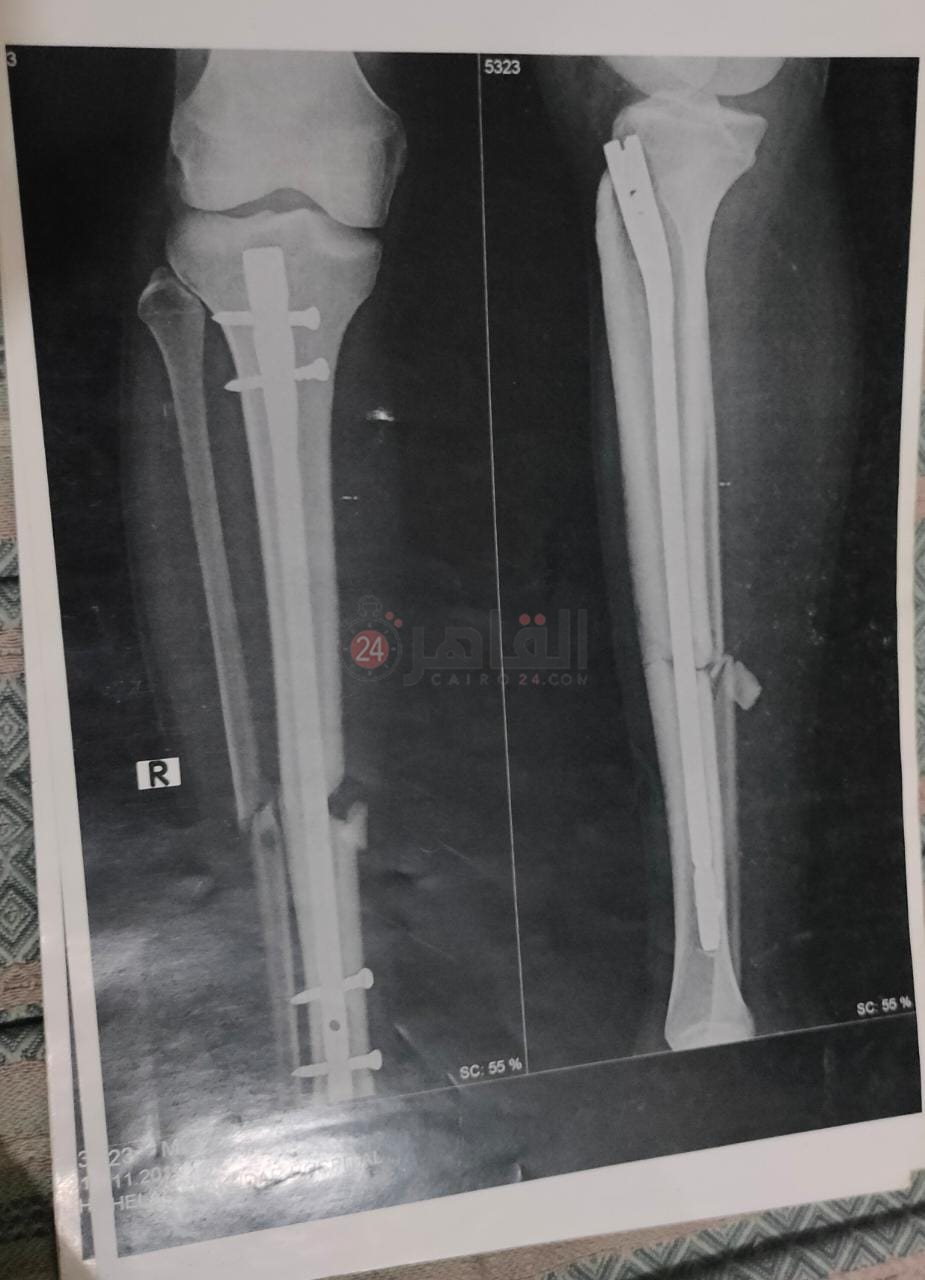

معاناة كبيرة يعيشها اللاعب السيد خالد صلاح، صاحب الـ23 ربيعًا، ابن وكابتن فريق كرة القدم بنادي "الصفوة" الرياضي بمدينة العاشر من رمضان بمحافظة الشرقية؛ بعدما تعرض لإصابة بكسر مضاعف في الساق اليمنى أثناء مباراة مع فريقه، قبل نحو 18 شهرًا، لم يتعافى منها حتى الآن بسبب خطأ طبي وإهمال وتقصير في نواحٍ عدة -على حد وصفه.

وأوضح اللاعب، والذي حملّ شارة القيادة طوال تسع سنوات بفرق كرة القدم بمراحلها السنية المختلفة بالنادي، أن الإصابة التي تعرض لها قبل عام ونصف العام نُقل على إثرها إلى المستشفى المتعاقد معه النادي، والذي طلب عدم ذكر اسمه، قبل أن يشير إلى أن طبيب المستشفى أجرى الجراحة له، لكنه اكتشف فيما بعدْ أن الجراحة تسببت في فقدانه الشعور بساقه، وبعدها، وفور الدخول في مرحلة العلاج الطبيعي مع أحد الأطباء المتعاقد معهم النادي، أصيب من جديد بحرق أسفل قدمه سببه “لمبة العلاج الطبيعي”، تسبب هو الآخر في تأثر أوتار القدم وانكماش أصابعه وعدم عودتها لحالتها الطبيعية من جديد، -وفق حديثه.

وأشار اللاعب، إلى أن أحد الأطباء الكبار، والذي سبق له العمل بالنادي الأهلي، أكد له على أن ما يُعانيه سببه الجراحة الأولى، والتي أخطأ الطبيب فيها بالتسبب في التصاق عظمة الساق بشظية القدم عن طريق ربطهما بمسمار طبي.